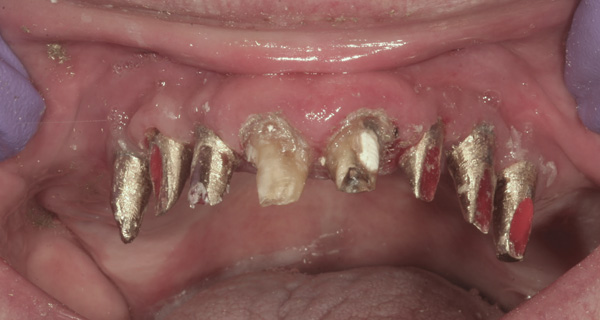

Case 1 – Re-preparing Abutments Intraorally

Background: This patient had a failing maxillary dentition and refused to wear a removable prosthesis. A staged approach was employed to retain some of his natural tooth abutments, and recession was noticed at the time of the impression for the second group of implants. Figure 1 shows the patient following insertion of the first set of implant custom abutments; the adjacent natural teeth are still present to support the provisional bridge. Seven months later, as shown in Figure 2, those first-stage custom abutments exhibited evidence of 1 mm to 3 mm of recession.

Figure 1  Patient following insertion of first set of implant custom abutments.

Figure 1

Figure 2 After 7 months, the first-stage custom abutments exhibited evidence of 1 mm to 3 mm of recession.

Figure 2